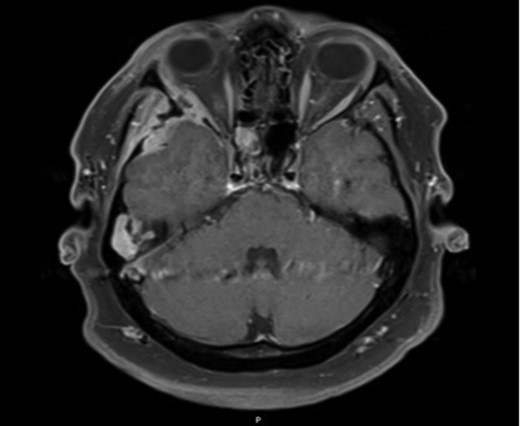

Axial CT images demonstrating bony involvement of the right mastoid and greater wing of the sphenoid.

Axial MRI image demonstrating ocular involvement, with abutment of right lateral rectus muscle, as well as enhancement of temporal lobe.

Due to the extensive nature of the findings, a magnetic resonance imaging (MRI) scan of the head was undertaken and demonstrated bony erosion of the lateral wall of the right orbit, right superior rectus muscle abutment and minimal involvement of the antero-inferior surface of the temporal lobe. The appearances were suggestive of fibrous dysplasia, chronic inflammatory/infective pathology or less likely metastatic carcinoma.